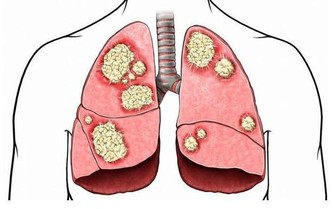

前列腺癌是男性常見的癌症之一,但和其他大多數癌症一樣,由於疾病發展緩慢,剛開始的時候可能沒有任何跡象,或者你根本注意不到這些跡象。

但是,當前列腺大到影響尿道時,症狀會變得明顯。這時候,你可能會開始注意到症狀,其中大部分與你上廁所的表現有關。從排尿需求增加到排尿困難,下面有7個症狀需要注意,它們包括:

如果癌症擴散到前列腺外,會出現其他症狀。這些症狀包括:

5. 其他癌症,患有膀胱癌、肺癌或甲狀腺癌的患者,出現前列腺癌的風險較高。